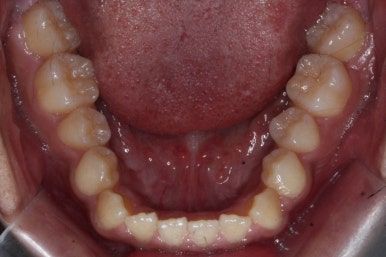

위 사진들은 부산주걱턱교정 키다리아저씨치과에 내원하셨을 당시의 입안 모습입니다.

입 안의 모습에서도 주걱턱의 특징으로는

하악이 앞으로 나와있습니다.

윗니는 뻐드러지고 아래 앞니는 뒤쪽으로 쓰러져 있습니다.

교합이 맞지 않습니다.